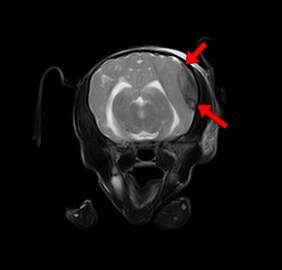

脑出血(图一) 脑出血(图二)